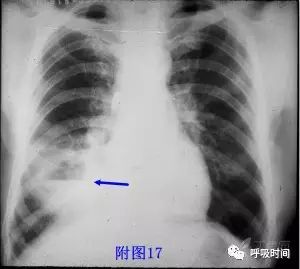

相对应的病变:肺脓肿、肺结核、肺癌、转移瘤、肉芽肿性血管炎(韦格肉芽肿)等(见图 17 ~ 图 20);无壁空洞鉴于干酪性肺结核。

图 17 肺脓肿:右肺中叶空洞,内可见气液平